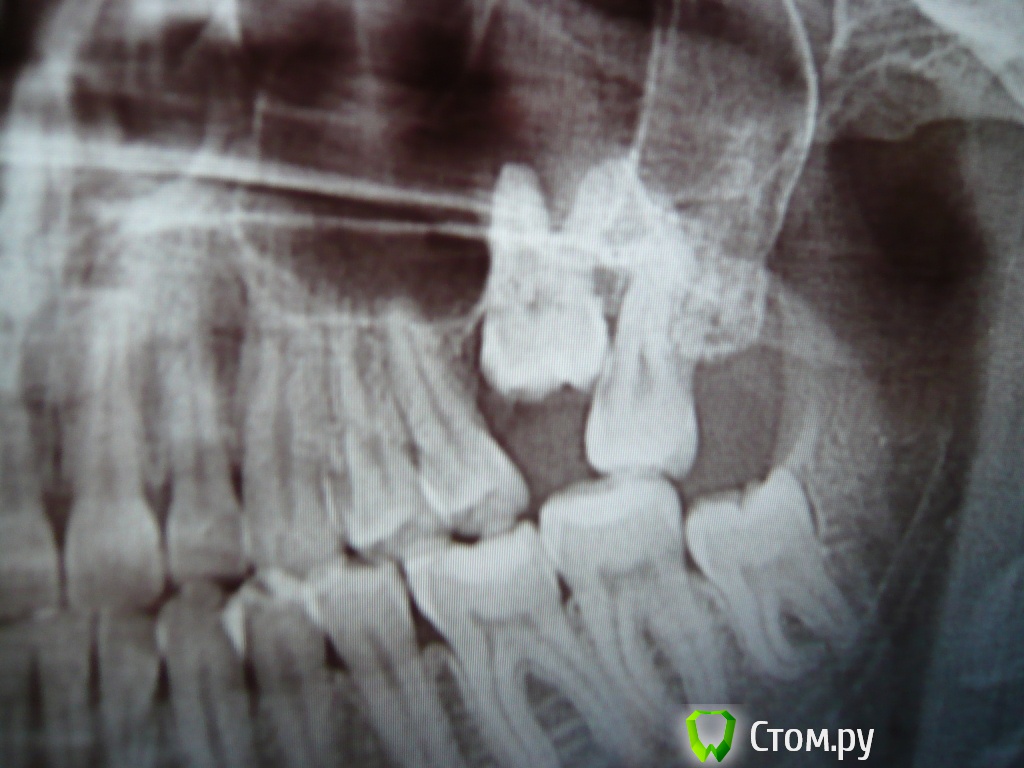

username1 Опубликовано 14 марта, 2014 Поделиться Опубликовано 14 марта, 2014 Доброго времени суток! Мне 23 года. Есть верхняя левая 6-ка, из под десны вылезла на ~ 3 мм. Уважаемые специалисты, прошу ответить на 2 вопроса: 1) целесообразно ли удалить верхнюю левую 7-ку с целью освобождения места для полноценного прорезывания 6-ки? 2) Какова вероятность естественного (без брекет-лечения) полного прорезывания 6-ки? Давно уже мучаюсь с 6-кой и 7-кой, не болят, постепенно появляется налет в области этих зубов, полноценная прочистка затруднительна, неприятный (тухлый) привкус в области этих зубов. Хочу разрешить проблему раз и на всегда. Заранее спасибо. Ссылка на комментарий